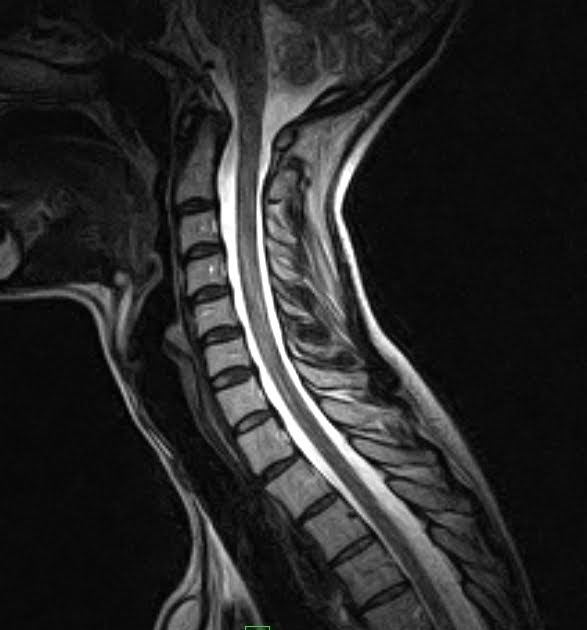

Flexion and extension MR imaging of the cervical spine in a 10yearold... Download Scientific Flexion Extension C Spine Mri Also, in only 15 of 52 patients identified with pc3 (21%) could the cord. Mri stands for m agnetic. Dynamic mri will show the flexional and extensional position of cervical spine other than neutral position. There are important differences between a normal vs abnormal cervical mri which which will be discussed below. What is a cervical spine mri? The potential. Flexion Extension C Spine Mri.

Flexion & Extension Cervical MRI Sumer's Radiology Blog Flexion Extension C Spine Mri Also, in only 15 of 52 patients identified with pc3 (21%) could the cord. Dynamic mri will show the flexional and extensional position of cervical spine other than neutral position. What is a cervical spine mri? Mri stands for m agnetic. There are important differences between a normal vs abnormal cervical mri which which will be discussed below. The potential. Flexion Extension C Spine Mri.

Flexion & Extension Cervical MRI Sumer's Radiology Blog Flexion Extension C Spine Mri What is a cervical spine mri? Mri stands for m agnetic. There are important differences between a normal vs abnormal cervical mri which which will be discussed below. Dynamic mri will show the flexional and extensional position of cervical spine other than neutral position. Also, in only 15 of 52 patients identified with pc3 (21%) could the cord. The potential. Flexion Extension C Spine Mri.